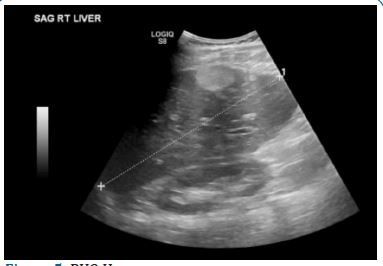

While in the ICU, the patient improved and did not have any further acute neurological events. Initial lab work on presentation showed normal CMP and troponins, and was pertinent for atypical lymphocytes, transaminitis. Daily labs showed a mild thrombocytopenia, improvement in the transaminitis, a normal urinalysis, and a negative urine drug screen. Daily labs on the date of discharge showed a mild thrombocytopenia and transaminitis. Neurology recommended an EEG which showed mild diffuse slowing with asymmetry and an MRI which showed no acute infarct or hemorrhage, midline shift, mass effect or evidence of acute ischemic stroke (Figure 4). Infectious disease recommended empiric vancomycin, ceftriaxone and acyclovir and virology was done confirming a positive EBV infection. Due to the patient’s symptomatic improvement, lumbar puncture was not done. Cardiology recommended 2D-echocardiogram with bubble study to rule out embolic stroke which showed a normal cardiac status. Gastroenterology was consulted due to mild transaminitis likely secondary to infectious mononucleosis and recommended a RUQ ultrasound, showing a 4 cm echogenic lesion in the right lobe (Figure 5). Over the course of the patient’s admission in the ICU, the patient did not endorse any neurological or cardiac complaints, reporting only a mild headache and vomiting with normal serial neurological exams.

Figure 5: RUQ Us.